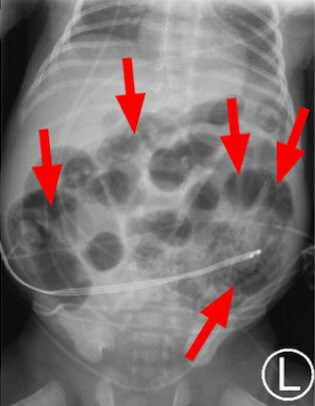

Necrotizing enterocolitis (NEC) is a common, serious intestinal disease that affects preterm infants, usually in the setting of a neonatal ICU. Traditional diagnosis relies on clinical manifestations, which can be subtle and sometimes develop too late to prevent major complications, or X-ray findings, as shown here. The red arrows show air in the intestinal wall, a sign of developing NEC.